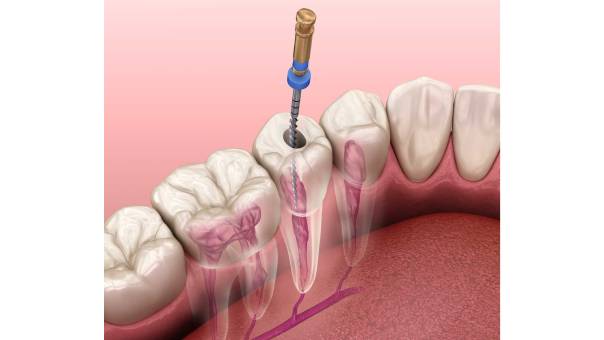

What is a Root Canal Treatment?A root canal treatment is a dental procedure designed to remove infected or damaged pulp tissue from within a tooth. The pulp is the innermost part of the tooth, containing nerves, blood vessels, and connective tissue. When it becomes infected due to deep decay, cracks, or trauma, it can cause severe pain, swelling, and eventually lead to tooth loss if left untreated.

The goal of RCT is to clean the infected area, disinfect the canals, and seal them to prevent further bacterial invasion. This allows the tooth to be preserved rather than extracted.

A standard RCT involves the following stages:

Locating the distal canal